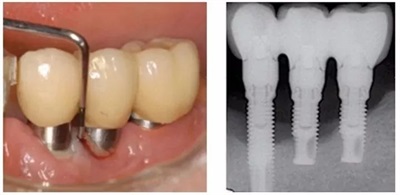

就像天然牙会有牙周炎一样,种植牙也会发炎、生病。种植体周围病包括种植体周围黏膜炎和种植体周围炎。

种植体周围黏膜炎 :局限于种植体周围软组织 ,主要表现为种植体周围牙龈的红肿、出血,是一种可逆性炎症病变,可逆并非指其具有自愈性,而是指通过积极口腔治疗后,种植体周围黏膜炎造成的病损可以被逆转。

种植体周围炎:病变造成骨结合丧失,破坏了种植体周围牙槽骨,主要表现除了种植体周围牙龈的红肿、出血,还有探诊深袋、骨吸收甚至溢脓、松动等表现。

前者可逆,后者不可逆,后者是前者进一步发展的过程。同样因为炎症导致骨吸收,不断的骨吸收,终可能导致种植牙脱落。